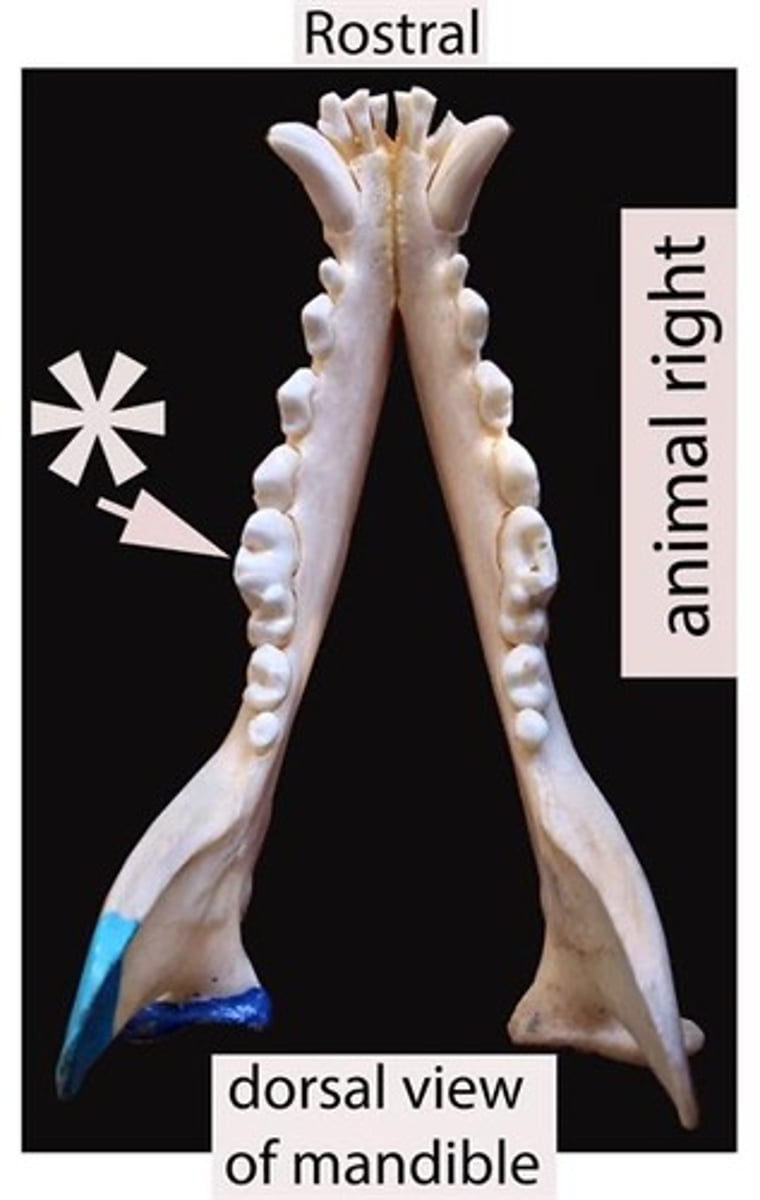

Identify the type of teeth shaded.

premolars

Identify the type of teeth shaded.

Canines

Identify the type of teeth shaded.

Molars

Identify the type of teeth shaded